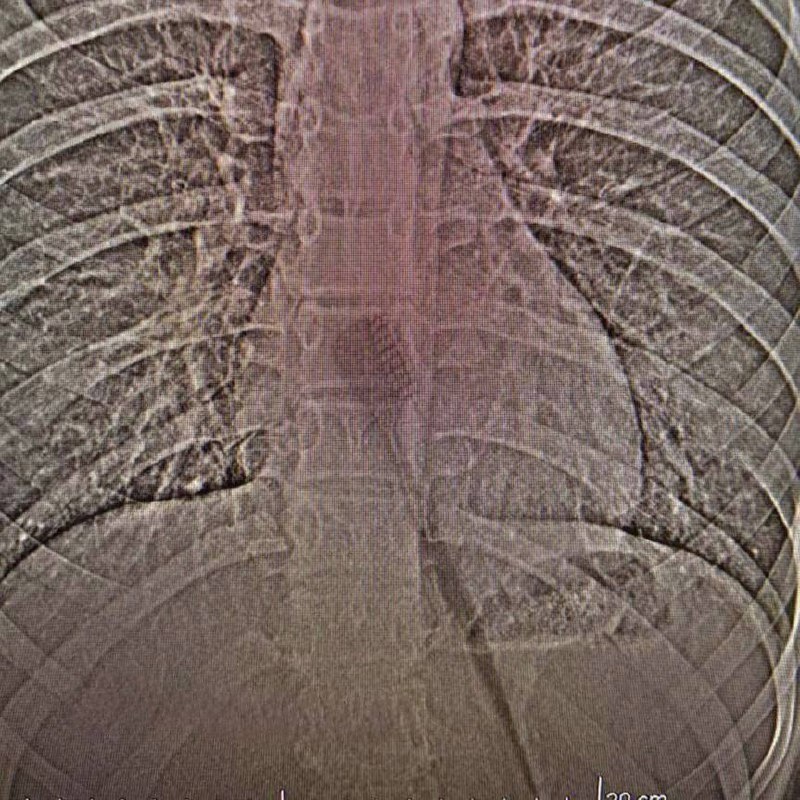

Привет, друзья! Сегодня обсудим случай, который заставляет задуматься о неожиданных поворотах в жизни. В Татарстане 13-летняя школьница случайно проглотила зубную щётку длиной почти 20 см. Представляете? Она полностью ушла в желудок из-за резкого вдоха или смеха во время чистки. Это не просто курьёз, а напоминание о том, как непредсказуема жизнь. Казалось бы, обычная ситуация, но какой неожиданный финал! Интересно, что могло произойти, если бы не экстренная операция? В любом случае, хорошо, что всё закончилось благополучно, и девочка уже дома. Но давайте задумаемся: как такое могло произойти? Может быть, это сигнал к тому, чтобы пересмотреть некоторые аспекты нашей повседневной жизни? Например, стоит ли смеяться во время чистки зубов? Или это просто случайность, которая не должна менять наши привычки?